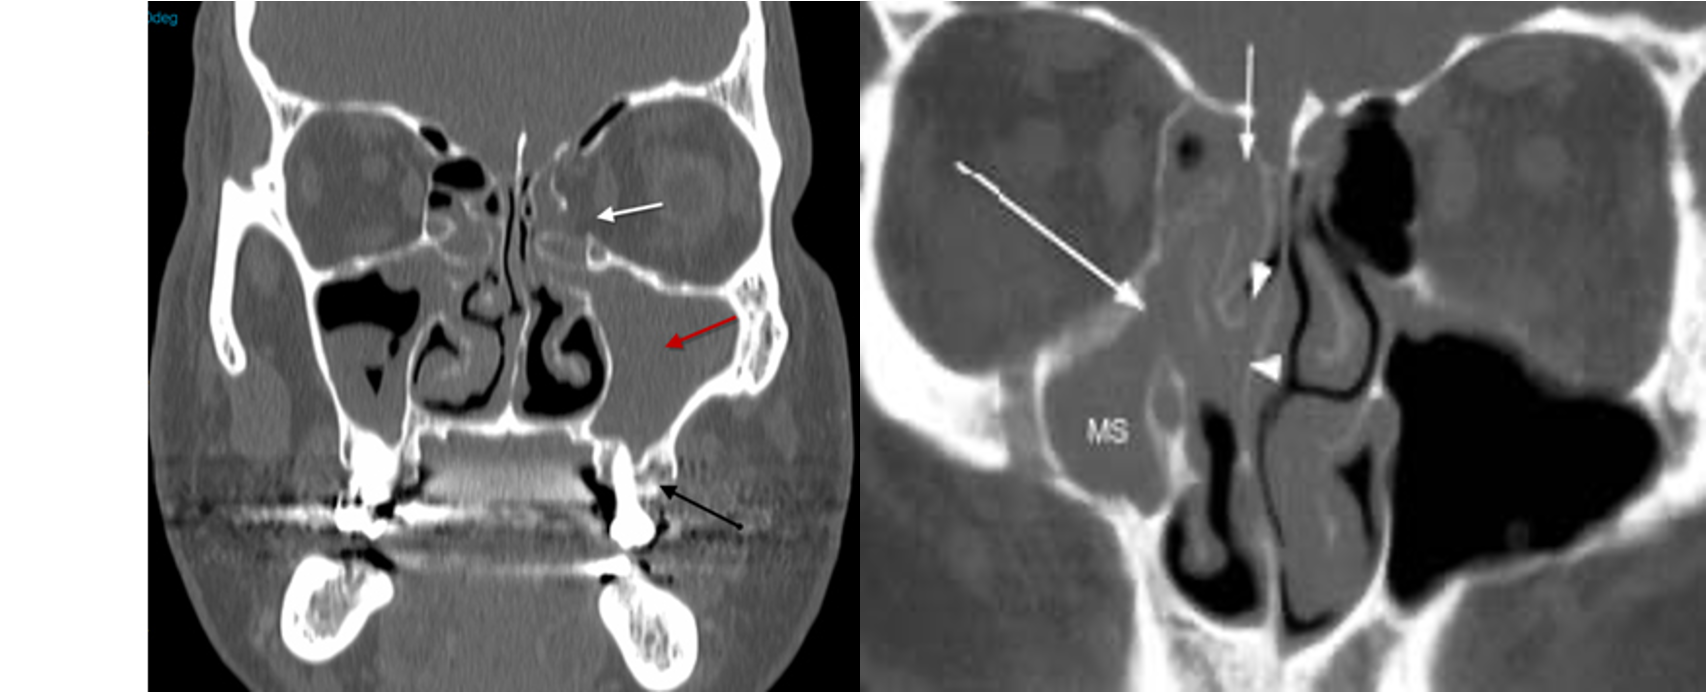

Chronic Rhinosinusitis

#ospe involved maxillary, ethmoid

Fungal sinusitis

heterogenous color, differences is fungal management is conservative; nasal spray, irrigation - no antifungals